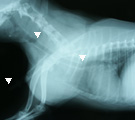

受診時。気管虚脱に対し気管内挿管の緊急処置が施されていた。 第1病日胸部X線写真。気管チューブを抜くと胸郭前口部で気管陰影消失(三角マーク間)。 引き続き、気管切開してシリコン製Tチューブを設置し気道確保した(マークはチューブ端を示す)。 第79病日、自己拡張型金属ステントに入れ替え、気管開存性と気道違和感が著明に改善した。

経過:町田夜間動物病院からの引継ぎで生命危機に関わる重度な気管虚脱であることが予想できたので、即座に慎重な治療計画を立てる必要性があった。気管内チューブ下では、違和感はあったが、room air吸入下でSpo2は97%を示し、肺機能は保てていた。Tチューブによる気道確保まで行う予定で万全の準備を整え、気管チューブを一度抜いた。予期していたとおり、ただちに呼吸困難とチアノーゼが生じた。すばやくビデオ透視と胸部X線撮影を実施し、ただちに麻酔導入し再挿管した。まず、将来的に自己拡張型金属ステント(Expandable metaric stent, EMS)を設置する可能性を考慮し、食道内にsizingカテーテルを挿入し気道内圧を20cmH2Oに保ち気管を拡張させX線撮影を行った。その後、気管支鏡検査にて、気管虚脱の範囲を同定し、また気管分岐部以降の虚脱がないことを確認した。Tチューブ設置のための気切部位は、X線所見と気管支鏡所見で同定した気管虚脱範囲の中点にあたる第5頚椎の部位とした。外径は輪状軟骨部の気管径の90%程度になるものを選び、8mmに決定した。気切孔から中枢側に大部分摺りこませ、口腔側へはガイドワイヤーを用い牽引して確実に引き寄せTチューブを設置した。設置後翌日より呼吸状態は改善し、食欲や一般状態もただちに回復した。術後管理は、1日2回のネブライゼーション(抗生剤、エピネフリン、生理食塩水、ステロイド)、Tチューブの気切部の栓を抜いて貯留痰の除去・吸引、1日2回の抗生剤の注射で行ったが、経過良好のため術後8日目に退院とした。自宅管理は、喀痰培養の結果に応じて抗生剤の処方を変えていったが、やはり入院時同様に1日2回のネブライゼーション、痰の除去、抗生剤の内服を継続した。Tチューブで管理中に、アメリカのEMSメーカーに気管sizingを含めた胸部X線写真の評価を依頼し、外径12mmX長さ52mmのステントを使用するよう指示された。ステント入手まで約1ヶ月程度を要した。しかしその間、軽度の咳がみられたがTチューブにて気管虚脱を十分よくコントロールできた。結局、オーナーと当院の都合が合い、犬の状態のよいときに(第79病日)、EMSへの交換を安全に無理なく行うことができた。EMS設置後、さらに状態は改善し、術翌日に非常に強く大きな声で吠えるになり、Tチューブ設置時より俊敏に動きまわるようになり、術後4日目に退院となった。第92病日、咳は消失した。